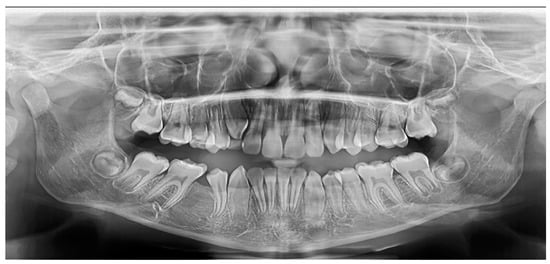

2.2.1. Case 1